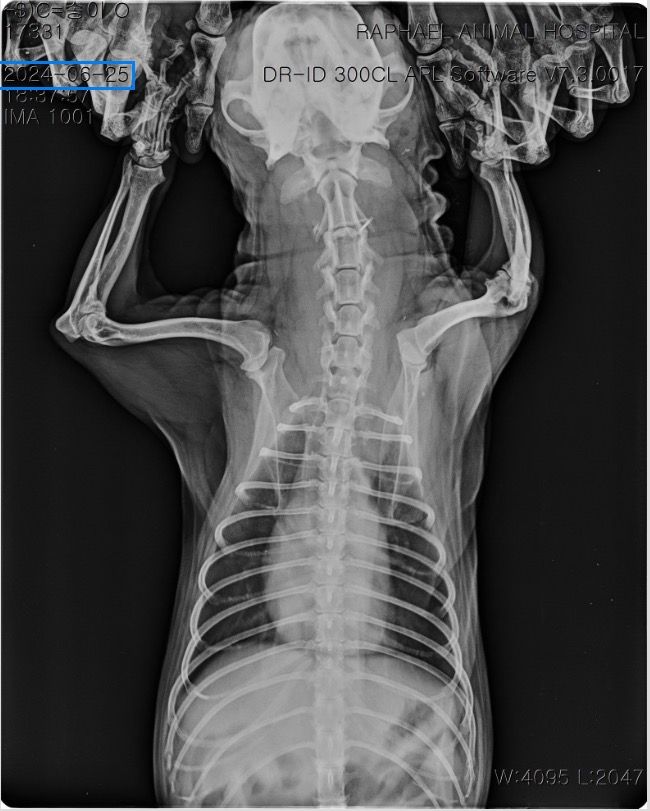

말씀주신 것처럼 보여주신 방사선에서 흉강 내 종양 (폐, 흉강 등)이 의심되는 상황입니다. 다만 방사선 사진만으로는 종양 여부와 정확한 위치, 개수, 성격을 완전히 판단하기 어렵고 CT 촬영을 통해 정확한 판단이 이루어져야 수술 여부 등을 결정할 수 있습니다. 좌측 폐는 앞엽과 뒷엽으로 나눠지긴 하고, 사진 상으로는 좌측 뒷엽 혹은 오른쪽 폐와 왼쪽 폐 사이에 있는 덧엽 부분에도 종괴가 위치하는 것으로 보이지만, 방사선으로는 어느 폐엽에서 발생한 것인지 정확히 구분할 수는 없습니다.

종괴가 단일 병변인지 여러 개인지, 정확히 어느 폐엽에서 시작되었는지, 주변 조직이나 다른 폐엽으로 이어져 있는지,

원발성 종양인지 전이성 병변인지 등을 알려면 CT 촬영이 필요하며 치료 방향도 CT 결과에 따라 달라집니다. 만약 한 두개의 폐엽에 국한된 단일 종괴라면 경우에 따라 해당 폐엽을 제거하는 수술을 고려하는 경우가 있습니다. 하지만 주변 조직으로의 침습, 원격전이 혹은 너무 많은 엽을 포함하고 있어 수술 후 호흡 합병증이 예상되는 경우 수술로 완치 기대는 어렵습니다. 빠른 CT 촬영을 추천드립니다.

사진상으로는 상당히 전형적인 원발성 폐종양의 방사선 양상이지만 말씀 하신 "방사선 엑스레이 촬영 한 것을 통해서서도

폐 종양인지 아닌지, 갯수를 확인가능한지

한 폐엽에만 있는 상황인건지 아니면 윗쪽 중간 폐엽과도 이어져있는지 원발성,악성 등등"에 해당하는 내용은 방사선 사진으로 평가하는게 아닌 흉부 CT검사로 확인해야 하는 사항들입니다. 흉부 방사선 검사는 저렴하지만 정확도와 세밀한 내용 평가에 제한이 있습니다. 우선 주치의와 상의하시고 흉부 CT검사를 촬영 한 후에 침습이나 전이 여부 평가하고 수술 계획 잡으시기 바랍니다. 원발성 폐종양인 경우 악성이더라도 수술로도 완치가 가능한 몇 안되는 질환이니 수술을 빨리 하면 할 수록 좋을 수 있으니 아이에게 주워진 시간을 아끼시기 바랍니다.